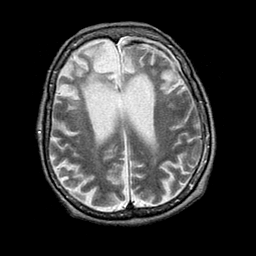

Pick's Disease, MR Study mr-t2 -- Slice #15

[Home][Help][Clinical] Slice 15